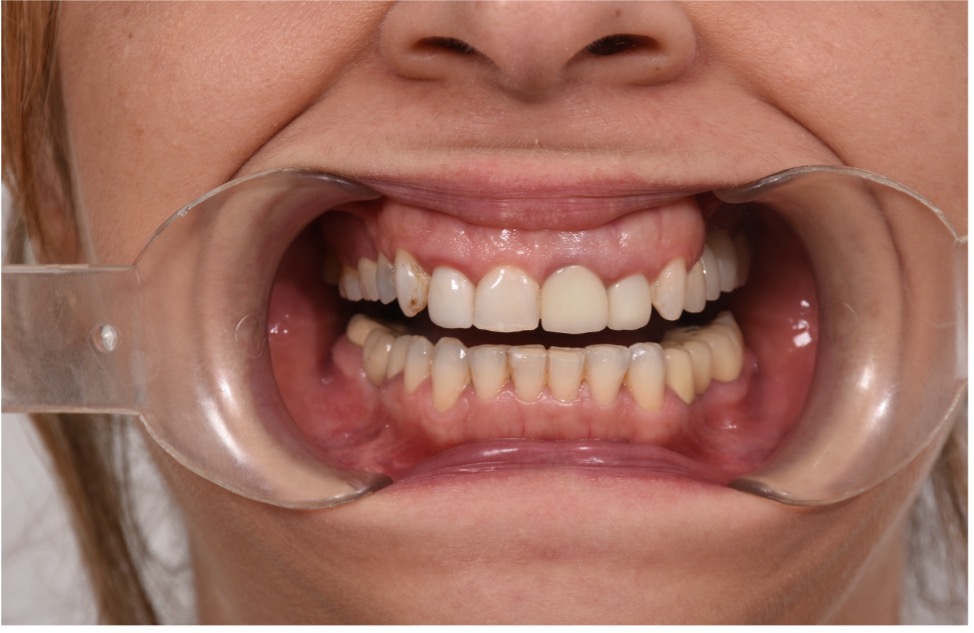

• Chief Complaint: Gummy Smile and Old Crowns

• Initial Diagnosis: Excessive Gummy Smile and Discolored old crowns

Step 1: Diagnostic Assessment and Smile Design The treatment began with a comprehensive evaluation of the patient’s smile using facially guided diagnostics. The Facial Flow Concept was employed to assess the relationship between the patient's facial structure, lips, smile arc, and gingival display. SmileFy software was utilized to generate a 2D digital smile simulation.

This visualization allowed both the clinical team and the patient to preview the planned esthetic outcome. It also provided a platform for mutual understanding and expectation management, forming a blueprint for all subsequent steps.